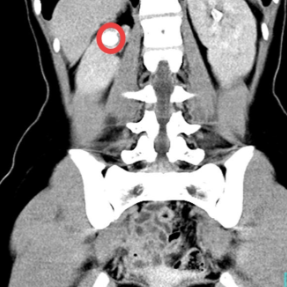

影像资料上可以看到女孩右侧多长了一个肾(红圈内)。

入院完善相关检查发现,小悦右侧有2个肾盂和2根输尿管,其中一根输尿管的开口位于阴道壁,绕过了膀胱这个“蓄水池”,同时也避开了尿道“阀门”的管控,导致“水龙头”关不住,长期漏尿。